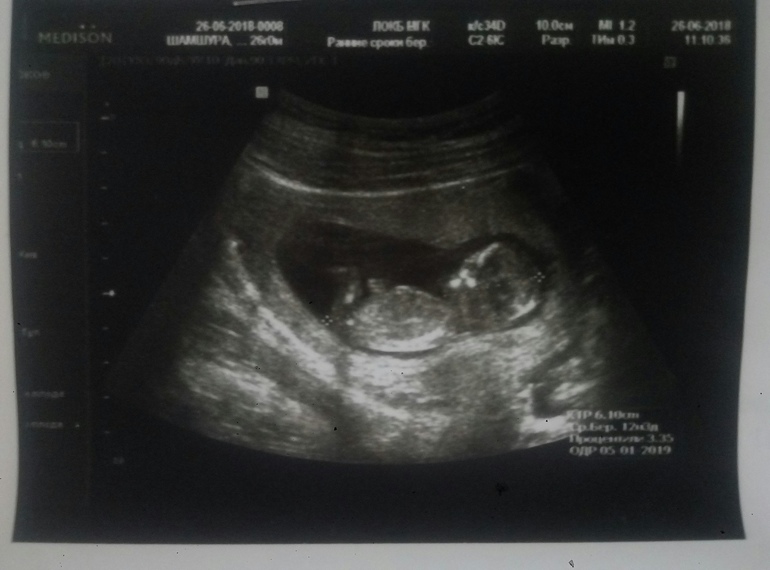

А вот и мы))))1-ый скриниг)

Результаты: УЗИ, КТГ, доплера, скринингаСегодня я познакомилась с нашим маленьким пузанчиком)))

Все хорошо, патологии исключили)

Дату родов назначили на 4 января))) Вот такой подарочек на Новый год и мужу на день рождения))))) Растем дальше)